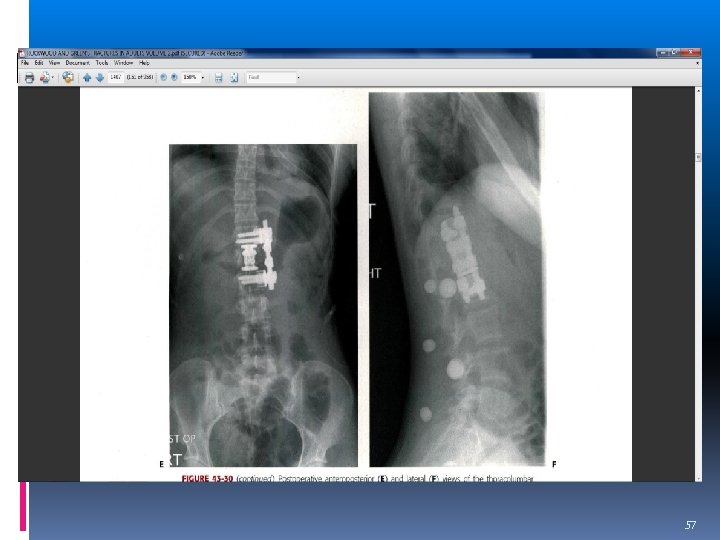

OPERATIVE TREATMENT (Ant vs post) Short segment posterior instrumentation the most common construct used, but specific construct design is dictated by the injury pattern and the neurology of the patient 45

SURGICAL APPROACH posterior approach is often favored with disruption of the PLC anterior approach in an incomplete neurologic injury with obvious anterior thecal sac compression. 46

POST APPROACH ONLY With PLC disruption Rotational and shear injury Canal compromise <50% with neurologic deficit 47

POST APPROACH ligamentotaxis 48

Short or long costruct? Advantage of short costruct Less fused segment Short surgical time Low cost Disadvantage High failure rate and psudoarthrosis 49

Always long Osteoprosis Sever kyphosis Thoracolumbar junction Sever comminution 50

Short costruct in Post app. Low lumbar FX 360 fusion 51

ANT APPROACH Canal compromise>67% and neurologic deficit Sever comminutted fx More than 5 days and neurologic deficit Kyphosis>30 and neurologic deficit Reverse cortical sign 52

Contraindication of Ant. Post instability 1. kyphosis>30 2. v. body collapse>50% 3. Translation>2. 5 mm 4. PLC disruption Sever osteoprosis Chest &abdomen injury Sever obesity &pulmonary disease L 4 -L 5 fx 55

57